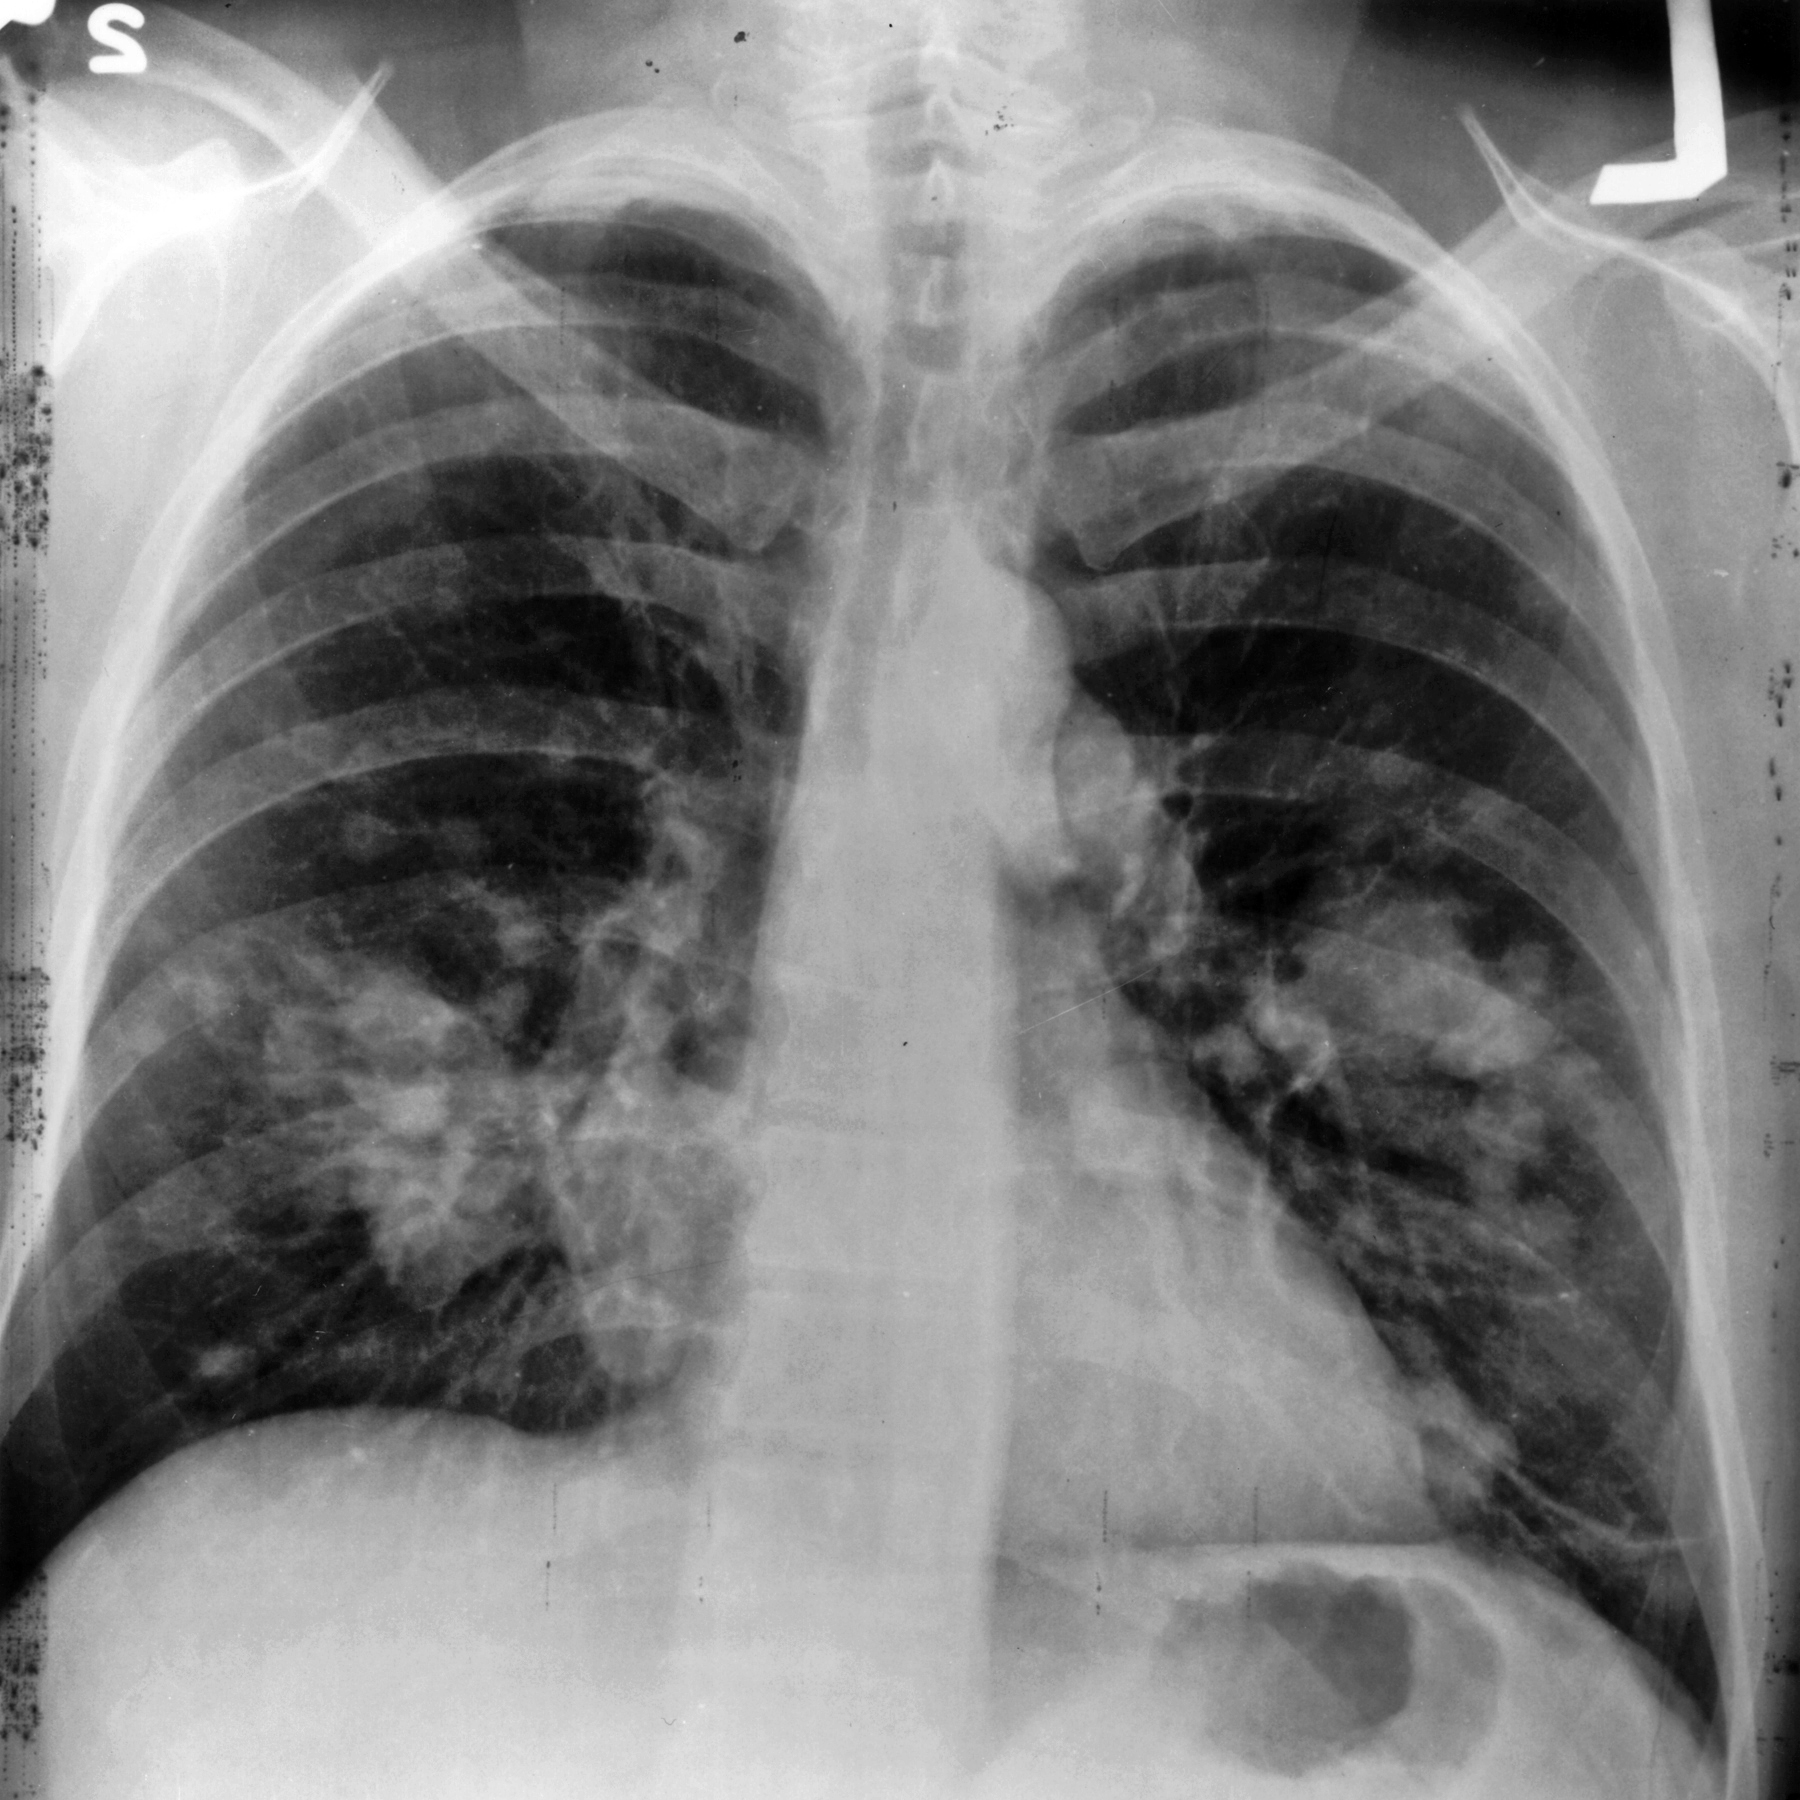

Bilecik Yeşilay, akciğer kanserine dikkat çekerek sigara ve hava kirliliğinin risk faktörleri arasında olduğunu vurguladı. Yapılan açıklamaya göre, her yıl dünyada yaklaşık 2 milyon kişi akciğer kanseri nedeniyle hayatını kaybediyor.

Türkiye’de akciğer kanseri, en sık görülen kanser türü olarak öne çıkarken, her üç kanser ölümünden biri bu hastalık nedeniyle gerçekleşiyor. Açıklamada, sigara, pasif içicilik ve hava kirliliğinin hastalığın en büyük tetikleyicileri olduğu belirtildi.